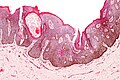

Seborrheic keratosis. H&E stain. | |

| LM | horn cysts, pigmented basal layer, hyperkeratosis |

Microscopic

Features:[2]

- Raised above skin surface.

- Border sharply demarcated.

- Hyperkeratosis - stratum corneum extra thick.

- Horn cysts - intraepidermal collections of keratin - key feature.

- Actually invaginations - not true cysts; thus, they may more accurately be called pseudohorn cysts.[4]

- Clusters of cells with brown granular material in the superficial dermis/dermoepidermal junction - pigmented melanocytes.

- Acanthotic seborrheic keratosis - thickened stratum spinosum; thick epidermis.

- Reticulated seborrheic keratosis - vaguely resembles fibroepithelioma of Pinkus (BCC, fibroepitheliomatous pattern).

- Irritated seborrheic keratosis - spongiosis (epidermal intercellular edema) and inflammation.

- Digitated seborrheic keratosis - papillomatous projections, architecture mimics a verruca.

- Stucco keratosis - pointed papillomatous projections.